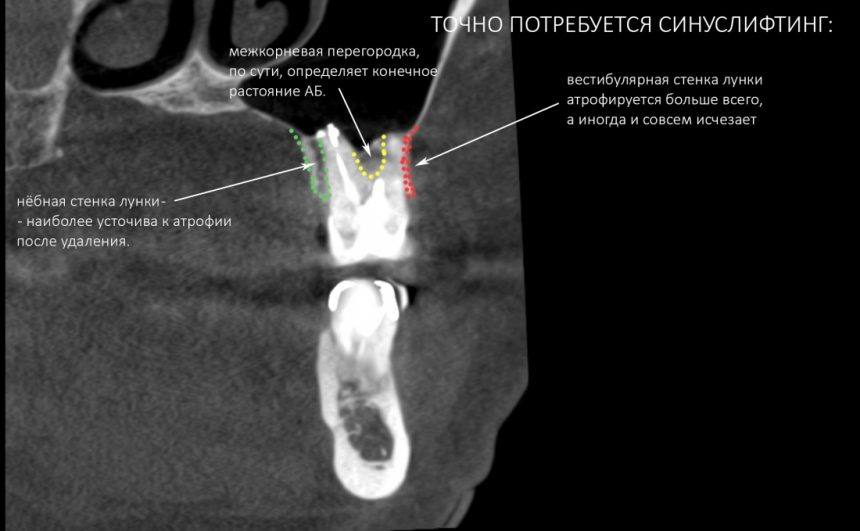

Простой синуслифтинг. Часть I.